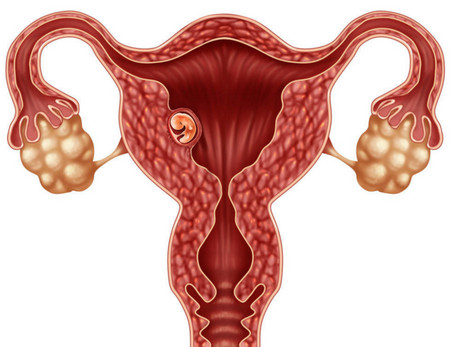

成功怀孕会经历以下几不同的阶段。- 精子必须到达并穿透并使女人的卵子受精。 - 产生的受精卵必须分裂并形成胚泡。 - 胚泡到达子宫并植入子宫内膜。 - 植入的胚泡...

不孕症是指结婚后至少1年,同居且有正常的性生活,在未采取任何避孕措施的前提下未能怀孕者,中国女性发生不孕症的几率为6%~15%。目前治疗不孕症的主要手段为试管婴儿...

孕妈妈怀孕后期进行了一些筛查,以帮助预防这些问题,或提早发现它们,医院会提供筛查的时间表,孕妈妈们要遵循医生关于治疗的建议,以便能安全的分娩和健康的婴儿。异位妊娠...